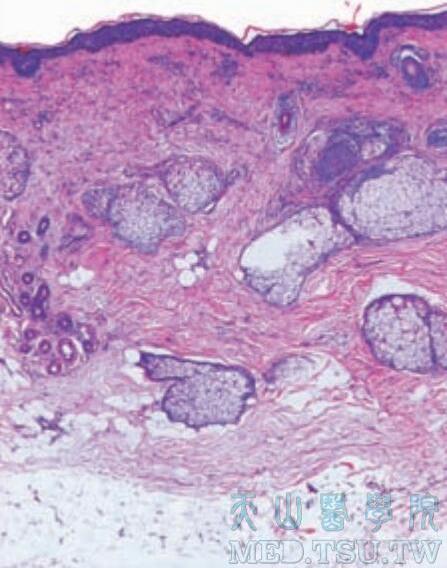

4皮肤附属器包括毛发、毛囊、汗腺、皮脂腺与指(趾)甲等。毛发与毛囊毛发: 毛发是由角化的角质形成细胞所构成,从内到外可分为三层: 髓质:是毛发的中心部分,由2-3层立方形细胞